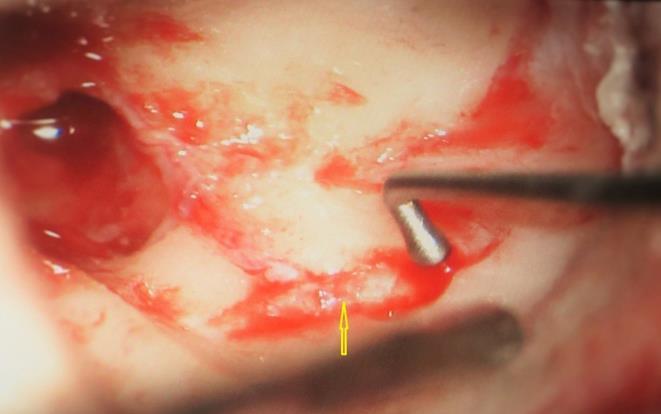

A 13 year old girl presented in ENT outpatient department with complains of recurrent right ear purulent discharge from pre and post auricular area for last 5 years. She had a history of incision and drainage in right post auricular area six months prior for similar complain. On local examination, there was right Grade II8microtia with atretic External Auditory Canal (EAC) and pre-auricular skin tag (Figure 1). A small fistulous opening was also seen in right cavum conchae region. Left ear examination was normal with intact tympanic membrane. Tuning fork tests using 256 and 512 Hz tuning forks showed moderate to severe conductive hearing loss in right ear with Rinne’s test positive in left ear. HRCT scan of temporal bones showed membranous atresia of right EAC with grade II microtia. Soft tissue density was seen filling the EAC and the entire middle ear cavity (Figure 2A). A CT based fistulogram done four months before our consultation identified multiple fistulous tracts situated in post auricular region and anterior to stylomastoid foramen in inframastoid region. These fistulous tracts were communicating through middle ear cavity (Figure 2B). There was associated erosion of posteroinferior and anteroinferior wall of EAC. Ossicles were dysplastic or eroded. Inner ear structures were normal. Patient underwent right radical mastoidectomy with wide conchal meatoplasty under general anaesthesia. Intraoperatively, there was right EAC membranous atresia with fistulous opening in cavum conchae. Cholesteatoma sac was seen filling the mastoid antrum area extending into middle ear cavity and EAC with erosion of posterior canal wall. Except remnant of malleus head which was fixed to epitympanic wall, no other ossicle was found. Oval window area showed bony depression without any overlying stapes footplate (Figure 3). Lateral semicircular canal bulge, facial nerve canal and chorda tympani were found at their usual locations (Figure 4). Obliteration of mastoid cavity posterior to vertical segment of bony facial canal was done using pedicled temporalis muscle flap to reduce the size of postoperative cavity. Middle ear cavity was covered with temporalis fascia graft.

Figure 4.Arrow pointing to exposed facial nerve (vertical segment)